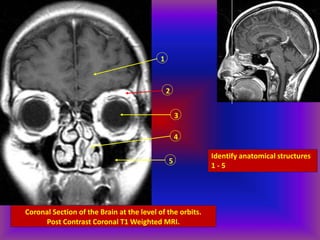

Coronal Section of the Brain at the level of the orbits.

Post Contrast Coronal T1 Weighted MRI.

1

2

3

4

5

Identify anatomical structures

1 - 5

1. Frontal lobe

2. Orbital Fat

3. Globe

4. Nasal Cavity

5. Maxillary Sinus